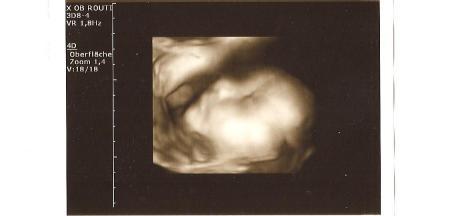

süße babys :) sehr schön!!!! und unser schatz in der 30ssw

Bild zu